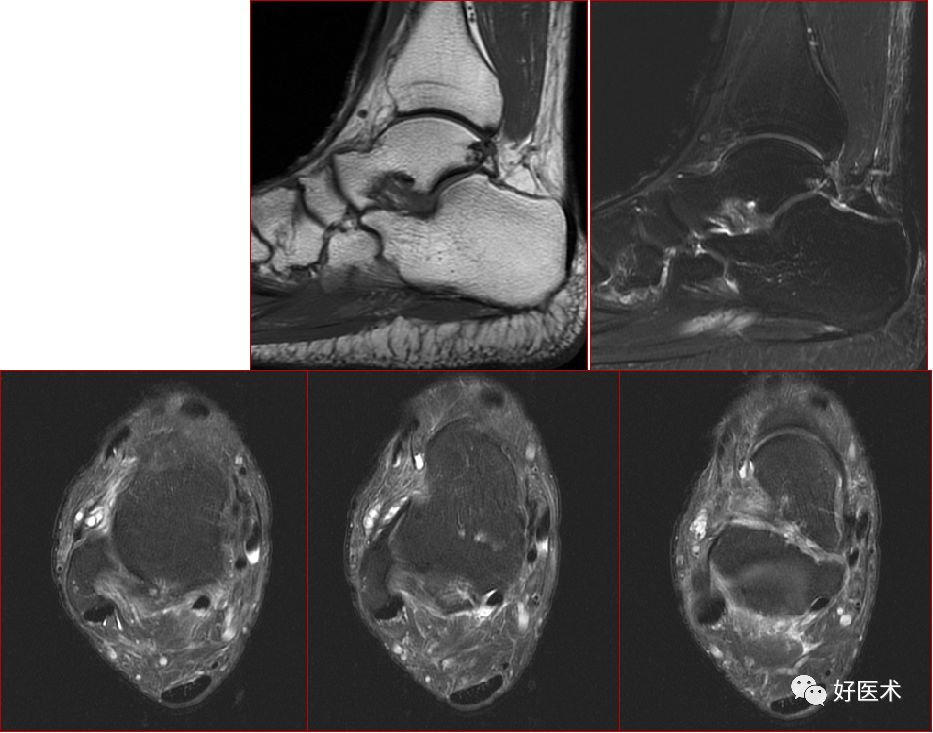

跟腱损伤

跟腱正常表现

跟腱运动损伤

跟腱附着处炎症

跟腱部分(完全)撕裂:跟腱最厚处前后径一般小于6mm,在踝关节上方2 – 6cm处跟腱纤维交叉走行,血液供应减少,易撕裂

慢性跟腱炎

跟腱炎症

慢性跟腱炎并跟腱部分撕裂

跟腱撕裂